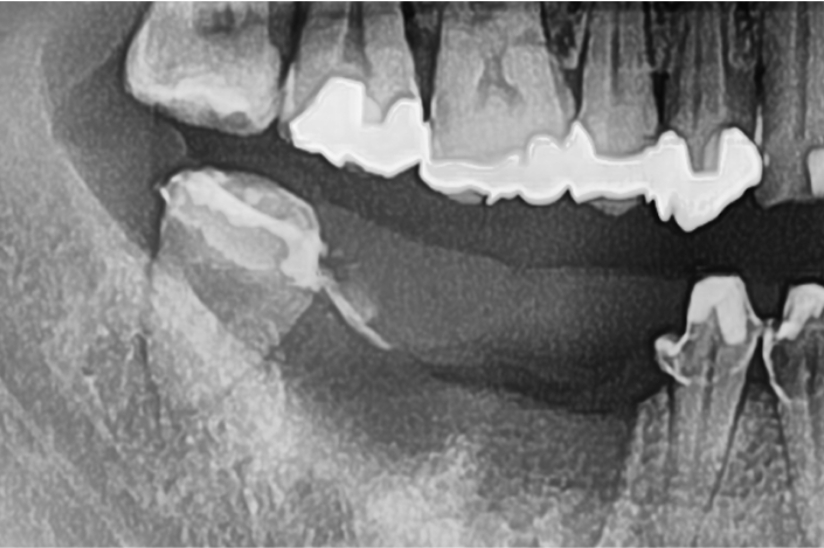

Before

Under Treatment

主訴

インプラントはできないが、入れ歯もしたくない

治療内容

自家歯牙移植 / イニシャルトリートメント(大臼歯)レジンコア

治療期間

3ヶ月

治療費用

550,000

治療の

リスク

術後しばらくしてから骨性癒着、外部吸収を起こす可能性があります。